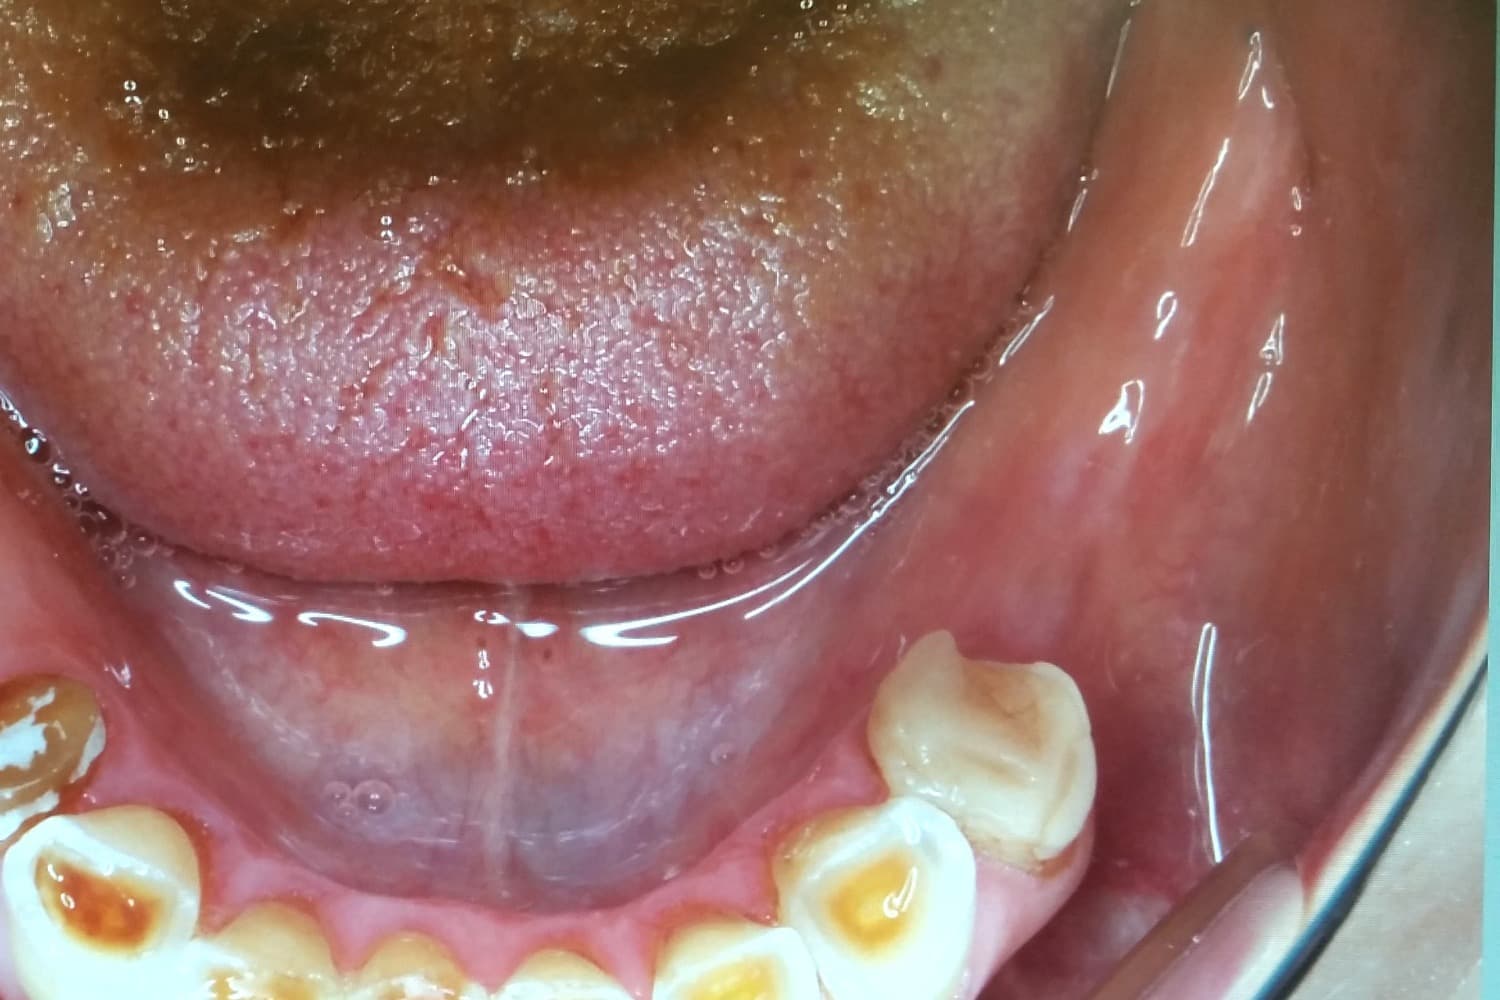

左下奥歯3本欠損部位のインプラント治療による修復

Before

左下奥歯3本の欠損部位をインプラント治療により修復をおこなう

年齢

40代

性別

女性

主訴

左下の歯がない箇所をインプラント治療したい

治療期間

4ヵ月

治療回数

5回

費用

825,000円

副作用・リスク

・骨の質や全身疾患によりインプラント体が骨と生着しない可能性がある ・術後に患部が腫れたり痛みが生じたりする可能性がある